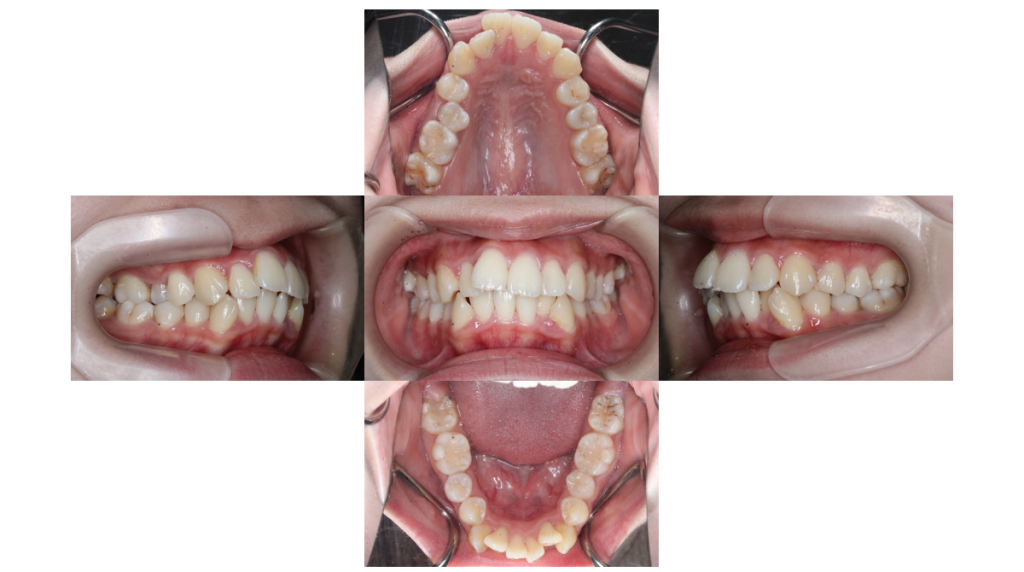

初診

叢生・裏側矯正の症例治療開始前の口腔内写真です。